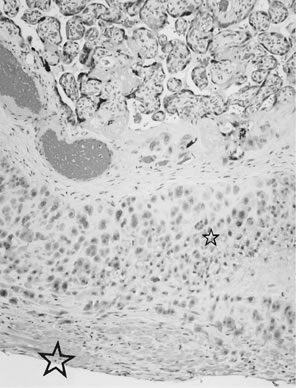

Placenta creta is a clinical diagnosis based on difficulty of delivery of the placenta. If the placenta is delivered and examined pathologically, areas of “incompleteness” of the maternal surface can be noted. The range of findings can extend from missing segments of the placenta to focal irregularities of the basal surface. At the edges of incomplete areas, histologic examination may yield smooth muscle (Fig. 10).61,62 This may be the only confirmation of a diagnosis of placenta creta that can be made when only the placenta is submitted to pathology. If a postpartum curettage or hysterectomy specimen is available, the diagnosis is usually confirmed. Histologically, the lesion may be very focal, with absence of decidualized endometrium, and villi implanted directly onto the myometrial smooth muscle (Fig. 11). The invasive trophoblast can be distinguished from endometrial stromal cells by immunohistochemistry; trophoblasts are cytokeratin positive and endometrial cells are vimentin positive. In a set of 462 births at less than 32 weeks' gestation and 108 singleton uncomplicated births at more than 37 weeks' gestation, excluding stillbirth, multiple gestation, chronic hypertension, diabetes mellitus, and fetal congenital anomalies, 44 of 462 (9.5%) of the preterm placentas had basal myometrial fibers versus 0.9% (1/108) of term controls (p < .001). Uteroplacental vessels with abnormal physiologic change were more frequent in cases with myometrial fibers (p < .003), and placental weights were lighter (p < .03). The incidence of basal myofibers was similar in preterm preeclampsia, premature membrane rupture, preterm labor, and nonhypertensive abruption.61 Experimental models suggest that cytotrophoblasts proliferate in response to hypoxia63,64 and may also directly migrate in response to local oxygen tension.65 One response to local hypoxia may be deeper myometrial invasion. Most of the foci of basal myofibers in our data set were found in the immediate vicinity of a uteroplacental vessel with incomplete or absent physiologic conversion. Basal myofibers may indicate local placental hypoperfusion that has prompted local deeper cytotrophoblast invasion.

Fig 11. A. Postpartum hysterectomy specimen. Normal implantation site with invasive trophoblast ( small star ), maternal decidua ( intermediate star ), and myometrium ( large star) (hematoxylin and eosin, ×10). B. Postpartum hysterectomy specimen. Placenta accreta with implantation of villi onto myometrium ( large star ). Few invasive trophoblasts ( small star) and no maternal decidua (hematoxylin and eosin, ×10).